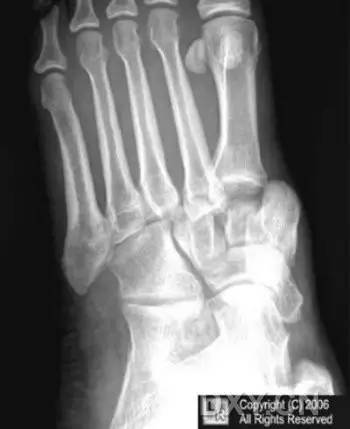

14.第五跖骨骨折

第五跖骨基底部骨折的不同类型:Stress 骨折;Jones 骨折:第五跖骨基底部以远 1 英寸内的骨折称为 Jones 骨折;Avulsion 骨折。

(来源:Radiopaedia)

Stress 骨折(来源:OrthoInfo-AAOS)

Jones 骨折正位片(来源:Radiopaedia)

Jones 骨折斜位片(来源:Radiopaedia)

第五跖骨骨折还有 dancer’s fracture。

dancer’s fracture 正位片(来源:footEducation)

dancer’s fracture 侧位片(来源:footEducation)